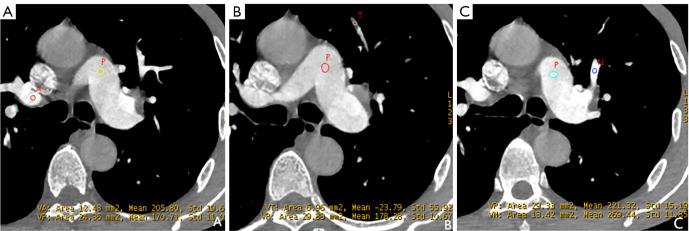

A total of 68 patients with PE who underwent DE-CTPA were retrospectively included. Quantitative parameters [slope of Hounsfield unit (HU) curves (Slope), CT values on virtual monoenergetic images (VMIs) ranging from 40 to 100 keV (HU-HU), normalized iodine concentration (NIC), and normalized effective atomic number (NEffZ)] on the BHA-induced low-density area of the right upper pulmonary artery (artifact), embolism, and the corresponding normal area of the left upper or right middle pulmonary artery (normal) were measured and calculated. The parameters among the three groups were compared, and the performances of the parameters in differentiating the three conditions were evaluated.

Quantitative parameters, including HU, HU, NIC, NeffZ, and Slope were all highest for normal arteries, followed by artifacts, and lowest for embolism (all P<0.05). To differentiate artifact and embolism, all parameters had areas under the curve (AUCs) higher than 0.80 (0.808-0.963), and HU had the highest AUC of 0.963. The multi-variables, combining HU, NIC, and NEffZ, had an AUC of 0.968, comparable to HU (P>0.05). Between normal and artifact, NIC showed the highest AUC (0.865), whereas multi-variables combining HU, NIC, and Slope improved the AUC to 0.937 and the model quality increased to 0.90 (P<0.05). For differentiation between normal and embolism, all parameters had AUCs higher than 0.80 (0.849-0.991); HU and HU showed the highest AUCs of 0.99 and 0.991, respectively. After a multivariable analysis combining HU, NIC, and Slope, the AUC was increased slightly to 0.995, which was comparable to that of HU and HU (P>0.05).

Quantitative parameters derived from DECT could recognize BHA in the superior vena cava; therein, 90 keV and 100 keV VMIs and their HU measurements would be particularly valuable.